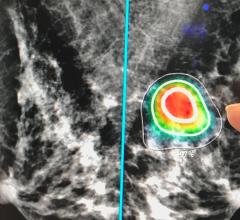

The picture archiving and communication system (PACS) channel features the latest news, videos and other content on this key information technology product category that serves as the backbone of radiology and medical image sharing. A PACS acts as a computer network for digitized radiological images and reports. Recent trends in PACS has moved away from standalone systems to enterprise imaging systems that integrate not only radiology, but all departments that generate imaging and image related reports so they can be centralized in one location and integrated into the over-arching electronic medical record (EMR). Related technologies include remote image viewing systems that allow images and reports to be accessed anywhere with a web connection, advanced visualization to reformat and perform measurement quantifications, and archive storage, which in recent years has focused on the use of remote cloud-based vendor neutral archives due to the vast amount of data storage required. Artificial intelligence (AI) is also being incorporated within all areas of PACS to increase efficiency.